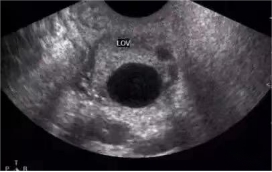

5.彩超监测卵泡发育情况:

B超下能直观的看到卵泡发育大小,是否成熟,大约何时成熟,指导备孕夫妇更好的把握同房时机。